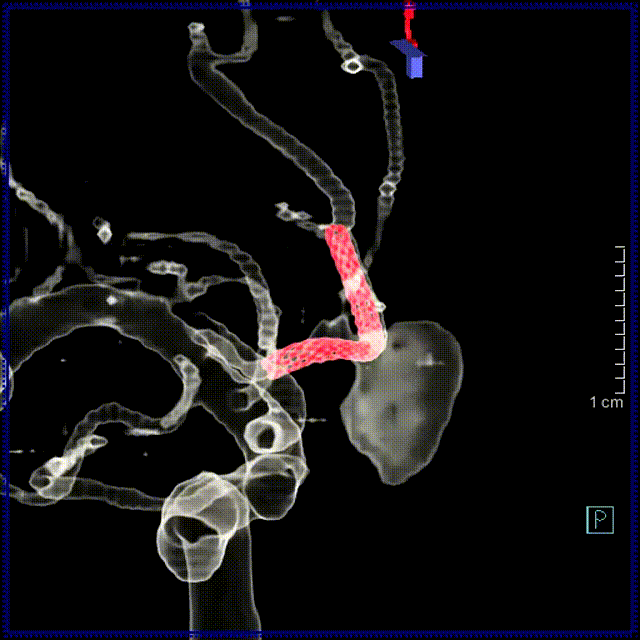

血流导向密网支架:Lattice 2.3-20mm

术后支架重建及血管融合

1. 载瘤动脉直径较小,支架微导管到位复杂,但微导管到位后,Lattice输送性好,未有明显血管位移;

2. Lattice支架可原位释放,远端定位精准且锚定充分,即使在细小血管中,打开贴壁也十分顺畅;

3. 支架前端导丝释放全程不位移,避免了对远端血管的伤害;

4. 支架释放后微导管无需上高后回拉输送系统,为远端血管的操作带来安全性;

5. 2.3mm是Lattice最小直径的支架,在细小血管中释放一气呵成,不需要反复推挤即可打开。支架尾端的释放也很稳定,打开充分。